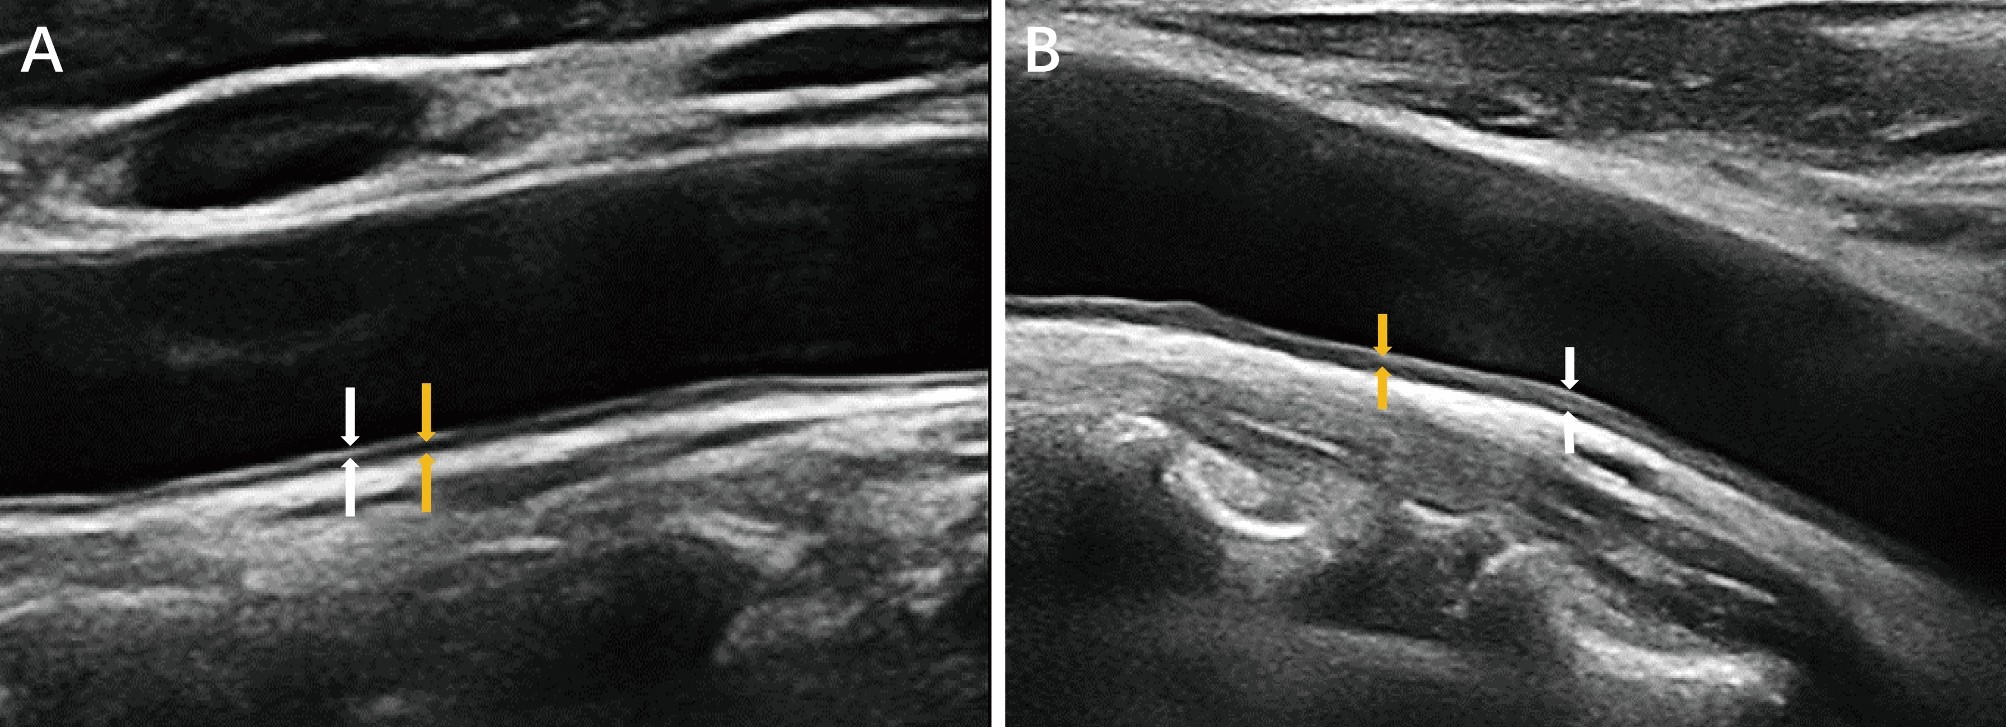

Fig. 2

From: Influence of remnant cholesterol levels on carotid intima thickness in type 2 diabetes patients

The high-frequency probe displays the measurements of carotid artery intima thickness (indicated by the white arrow) and media thickness (indicated by the yellow arrow). (A) Control group; (B) high RC group.